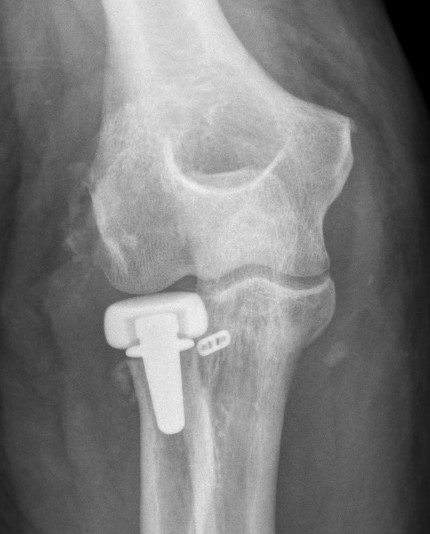

coronoidCoronoid Buttress Plate AP

Medial approach and buttress plate with LCL repair

buttress plate

Universal posterior approach with radial head replacement and medial approach with medial buttress plate